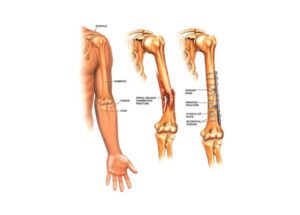

Las fracturas óseas pueden variar en gravedad, desde una simple fisura hasta una rotura completa en varias partes. El tipo de fractura influye en las opciones de tratamiento. Las fracturas capilares o por estrés son pequeñas fisuras difíciles de detectar, mientras que las fracturas completas rompen el hueso en dos partes. Las fracturas abiertas implican que el hueso atraviesa la piel, y las fracturas conminutas significan que el hueso se ha fragmentado en múltiples piezas.

Una fractura ósea es evidente si el hueso sobresale a través de la piel, pero en otros casos, puede ser menos obvio. Los síntomas incluyen dolor intenso, hinchazón, moretones, dificultad para mover o soportar peso en la extremidad, y en algunos casos, deformidad o un ángulo anormal de la extremidad.

El objetivo del tratamiento de las fracturas es permitir que el hueso sane y se fusione de nuevo. A menudo, esto puede lograrse inmovilizando el hueso durante varios meses con la ayuda de una escayola y una férula. Cuanto más grave es la fractura, más probable es que se recomiende la cirugía.

Por ejemplo, una fractura abierta o conminuta requerirá una intervención quirúrgica para garantizar que el hueso vuelva a crecer por completo y soporte su peso con seguridad. La reparación quirúrgica implica el uso de varillas, tornillos o placas metálicas para fijar el hueso en su sitio o alinearlo mientras se cura.